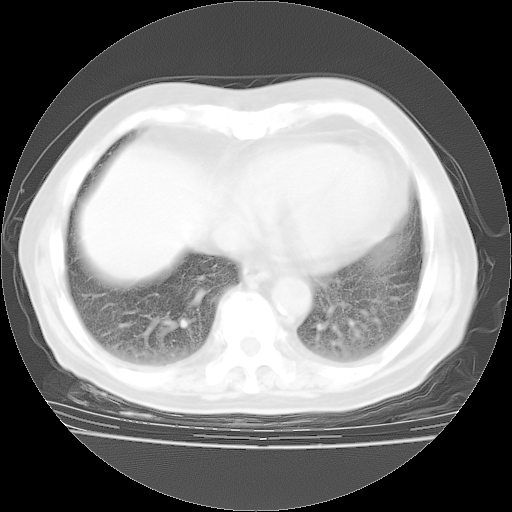

4月28日肺部CT——再次出现类似去年5月9日——透光度降低,“间质性”改变。

4月28日肺部CT——再次出现类似去年5月9日——磨玻璃样、间有“粟粒样”改变。